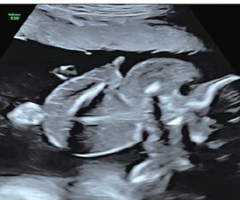

超声诊断胎儿右冠状动脉-右房瘘1例

[中图法分类号]R445.1;R714.5 [文献标识码]B 孕妇29岁,孕29周,孕2产0,因外院产前检查发现胎儿心脏结构异常来我院就诊。自诉孕前尿红细胞增多1年,未行特殊治疗;无心血管疾病家族史及遗传病史。产前常规超声检查:宫内单活胎,...